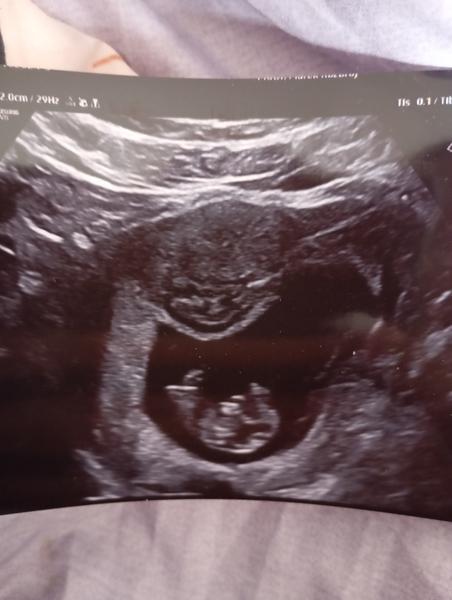

Je myom během těhotenství nebezpečný pro matku i dítě?

Ahoj . Já mám také myom 1.4mm předchozí Dr co jsem měla před změnou mi ho nenašla. Zjistili mi ho v 10 TT . V genetu mi vysvětlili že se může zatáhnout jak poroste děloha . Musí se hlídat aby nerostl . Neboj . Vše dobře dopadne. Jen si hlídej aby ti ho Dr kontrolovala

Celou dobu tam nic neviděli, az najednou teď nechápu. Minulý týden jsem taky byla na utz a nic